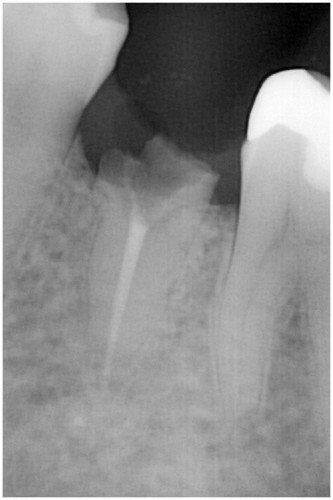

術前

被せ物の二次虫歯と根の破折

抜歯後